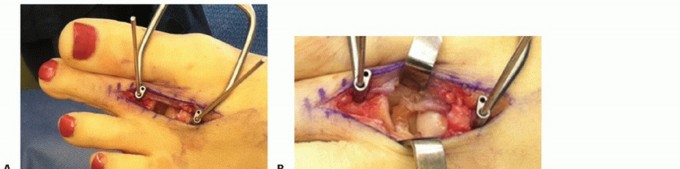

If no diagnostic arthroscopy is performed, a dorsal 3-cm longitudinal incision is made over the second MTP joint, the extensor tendons are retracted or elongated (Z-plasty), and the capsule is incised to expose the MTP joint. A Weil osteotomy is then performed as described earlier to allow full visualization of the plantar plate.

Visualization of the plantar plate can be further enhanced with longitudinal traction or various other distraction techniques (TECH FIG 7A).

- TECH FIG 7 • A. Distraction across the MTP joint after performing a Weil osteotomy. B. Identification of the plantar plate rupture at the base of the proximal phalanx. C. Suture is passed through the plantar plate, and the bone tunnels are prepared in the proximal phalanx. D. The completed plantar plate repair with fixation of the Weil osteotomy.

Completion of the plantar plate tear may be necessary if a direct repair of the partial tear is possible. This should be performed as close to the phalanx as possible when needed.

The plantar surface of the proximal phalanx is roughened with a rongeur or curette to facilitate healing of the repair to the bone.

The plantar plate tear is then identified (TECH FIG 7B) and the plate needs to be mobilized to allow for repair with longitudinal or transverse sutures in mattress fashion based on the orientation of the tear.

Two vertical holes are then drilled using a K-wire in the proximal phalanx from dorsal to plantar (TECH FIG 7C). These should exit the plantar phalanx just below the plantar surface.

The sutures from the plantar plate repair are then shuttled through these holes from plantar to dorsum and tied over the top for fixation with the toe held in 20 degrees of plantarflexion.

The Weil osteotomy is then stabilized as described earlier (TECH FIG 7D) and any soft tissue corrections may also be performed at this time.